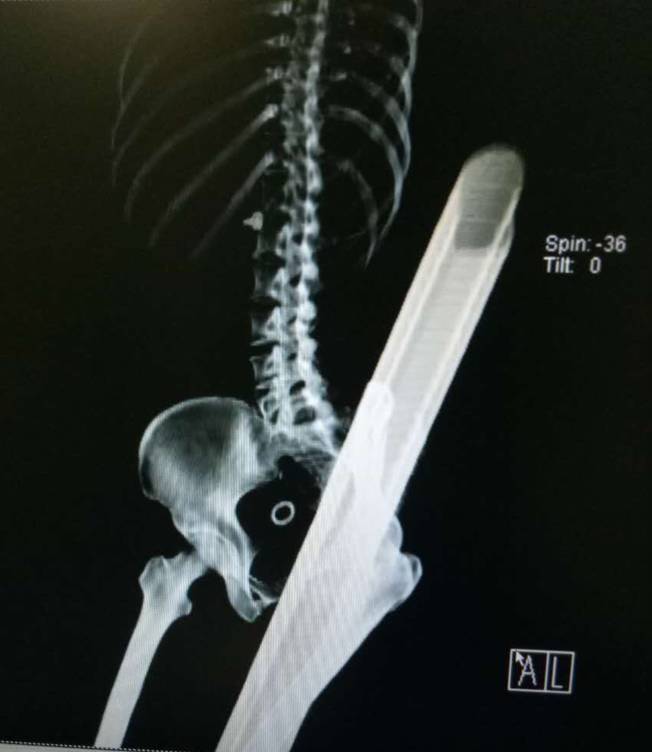

据珠海市人民医院CT检查结果显示,一根护栏的铁管从该女子的会阴贯穿至左边臀部,以至于会阴及直肠受损;还有一根铁管从左大腿贯穿至左侧腰背部,大腿内侧产生了长至12厘米的伤口。同时,左边小腿同样被贯穿。据现场图片显示,护栏的铁管竟有手臂粗细。

CT检查结果可见,贯穿至体内的钢管比骨头还粗